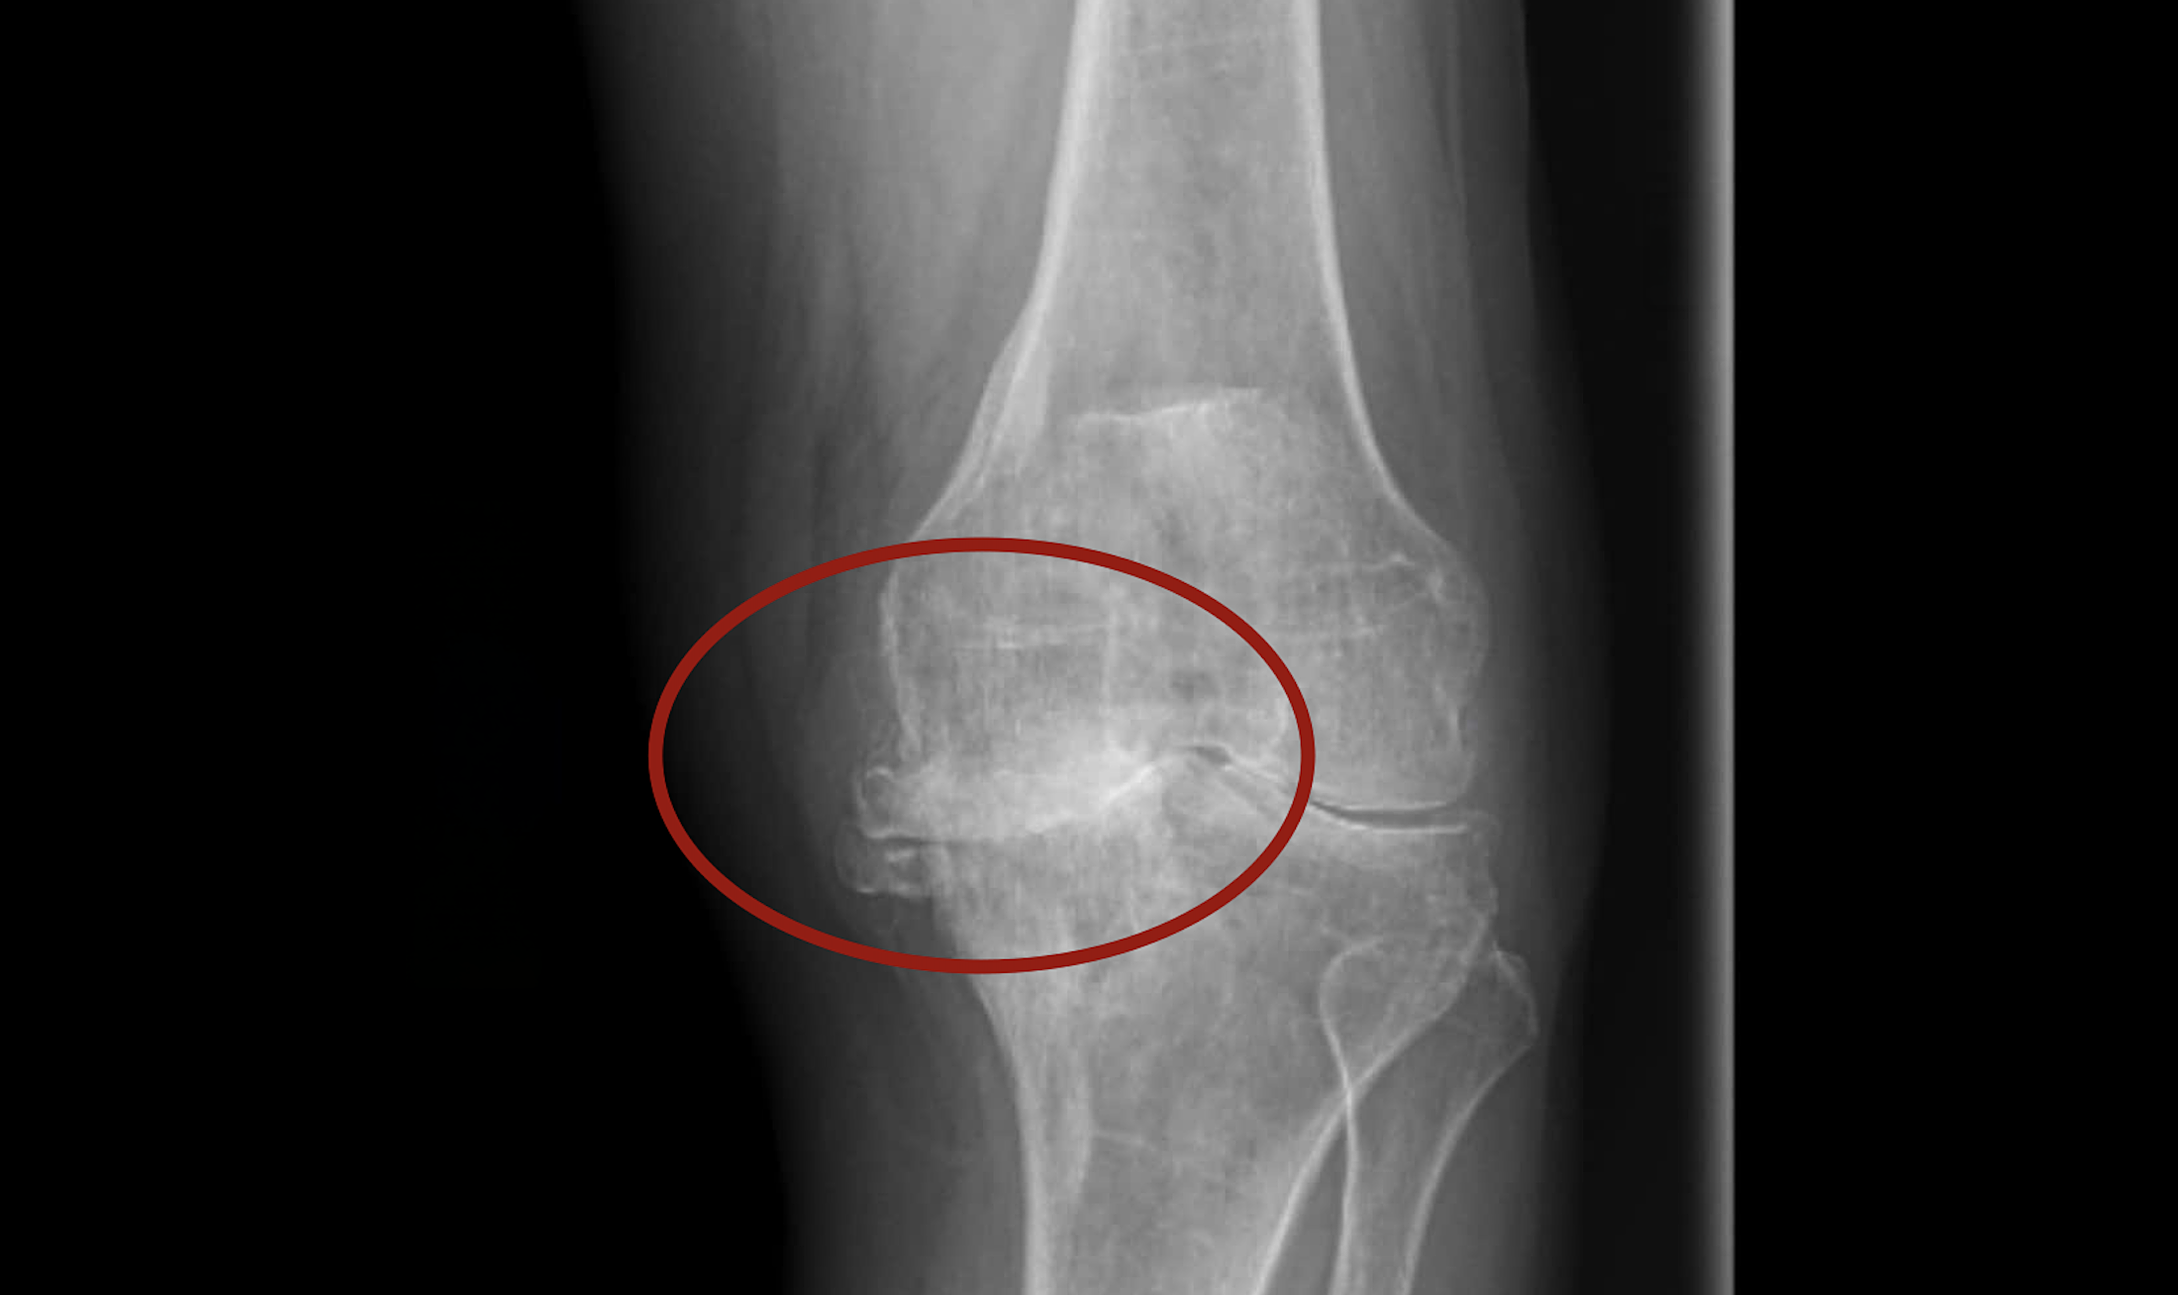

Recently, as her joint pain and swelling intensified, Ms. Hong visited Tam Anh General Hospital, Ho Chi Minh City. X-rays revealed end-stage left knee osteoarthritis, severe deformity, a 15-degree axial deviation, complete cartilage loss, subchondral bone damage, and medial tibial plateau bone loss. The patient also suffered from impaired liver and kidney function, leading to early-stage chronic kidney failure. Doctor Hoc attributed these complications to "the patient's self-medication with numerous drugs over a long period."

X-ray results showed Ms. Hong's knee joint suffered severe damage, with bone ends directly rubbing against each other. *Tam Anh General Hospital* |